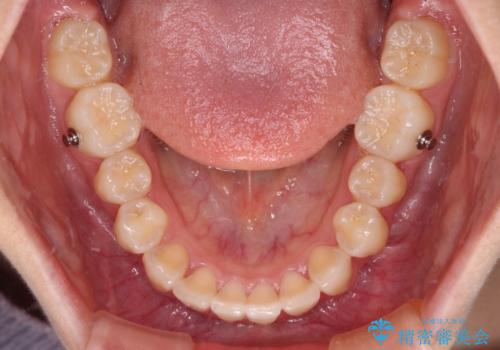

インビザライン単体で対応することも検討できますが、達成する可能性が低いため、カリエールディスタライザーという補助装置を併用して、より確実性を上げることとしました。

インビザラインをしっかりと装着したことはもちろん、高校生は歯の動きが早いため、非常に短期間で治療を終えることができました。